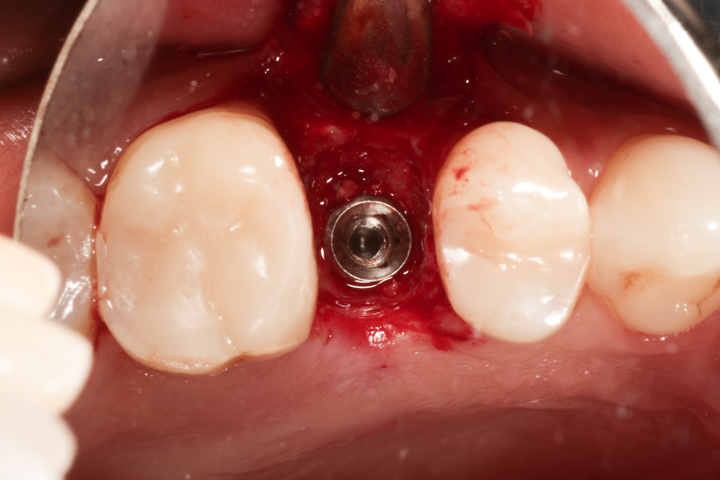

Alternatywą dla mostów są implanty, które pozwalają uzyskać całkowicie nowy ząb bez ingerencji w zęby sąsiednie. Mogą być zatem czyszczone nitką po obu stronach, lepiej prezentują się w strefach estetycznych. Ich wady to wyższa cena, dłuższy czas leczenia i wrażliwość na niedostateczną higienizację. Poniżej zamieszczam kilka przykładów wstawiania zębów za pomocą implantów.

Jest to standardowa procedura wszczepiania implantu i jego odbudowy ze wszystkimi etapami pośrednimi począwszy od usunięcia zęba do cementowanej korony.

Poniżej przykład implantacji natychmiastowej tzn. takiej gdzie implant zostaje wszczepiony zaraz po ekstrakcji uszkodzonego zęba. Zaletą tej metody jest fakt, że zamiast dwóch zabiegów chirurgicznych, jest jeden.